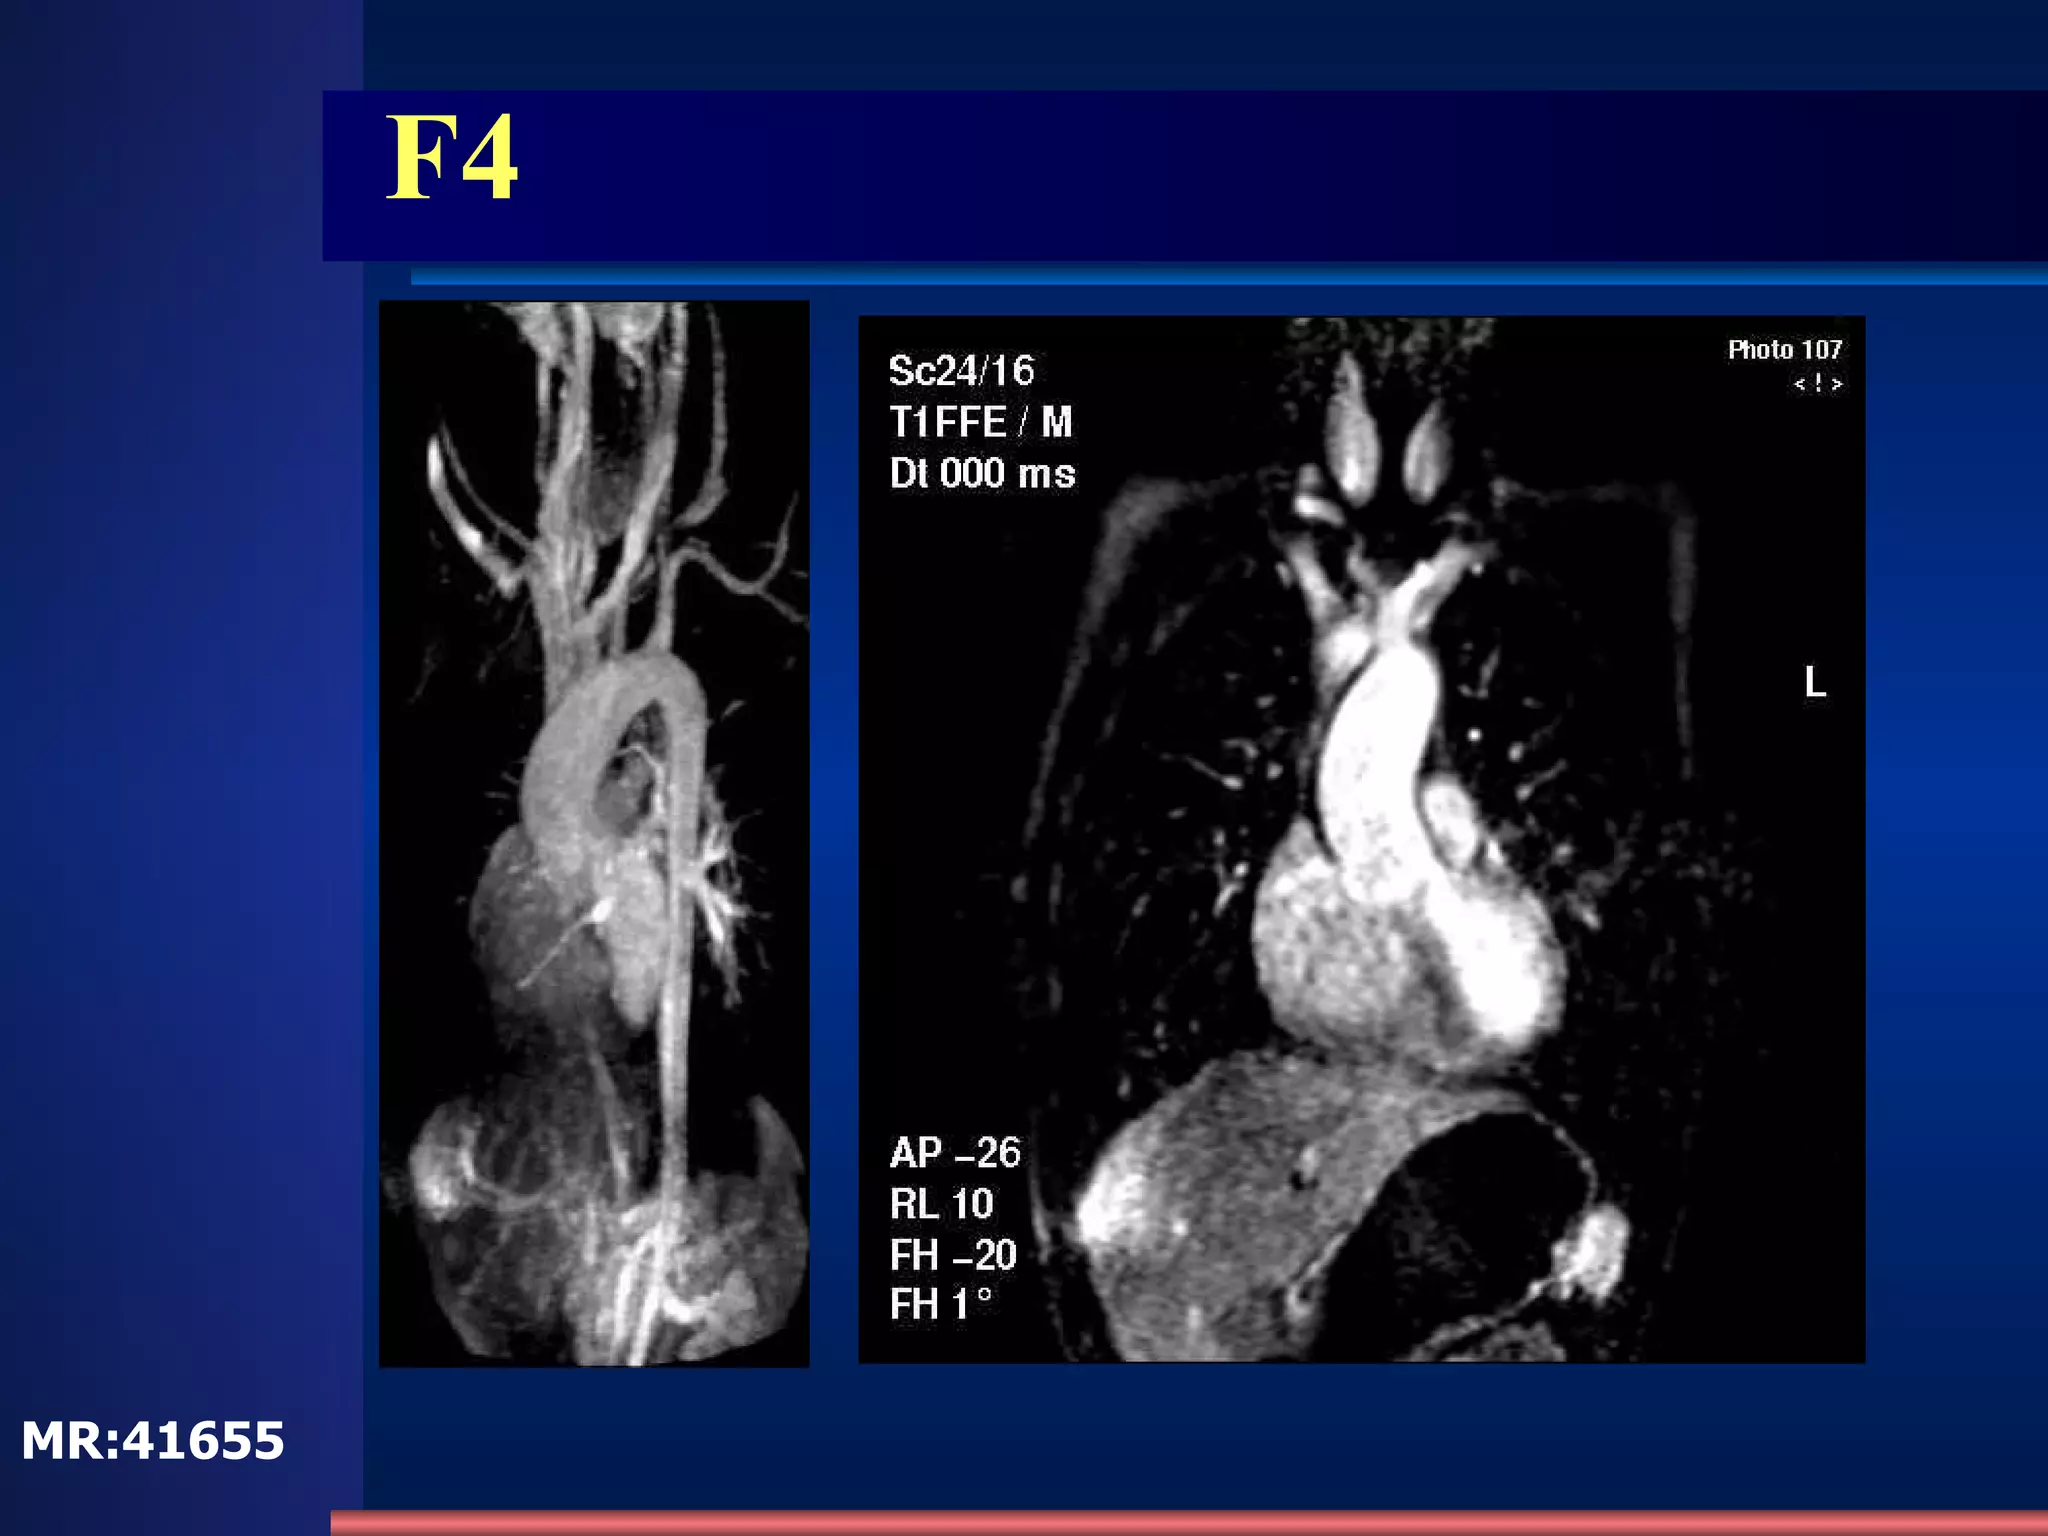

F4 Aortic overriding Pulmonary stenosis right->left shunt RV hypertrophy LA RV MR:41655

F4 MR:41655

F4 Aortic overridingPulmonary stenosis right->left shunt RV hypertrophy LA RV MR:41655